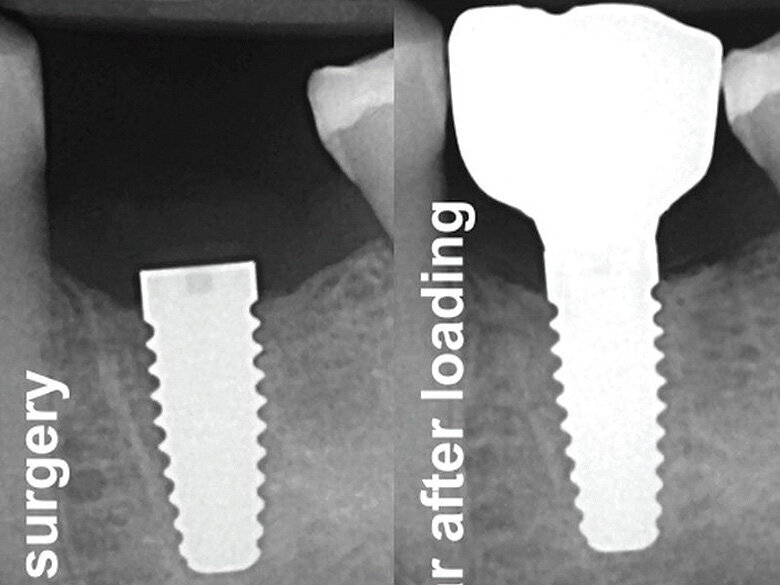

Fig. 13: X-ray control after surgery and one year post-loading. (Photo: Jens Tartsch, DMD)

This case shows a ZERAMEX XT 4.2 x 10 mm implant placed in a healed extraction and grafted site. The implant placement was done four months post-tooth extraction and grafting.

At the one-year follow-up with the patient, the implant shows no peri-implant inflammation. In addition, no movement or bone loss can be observed.